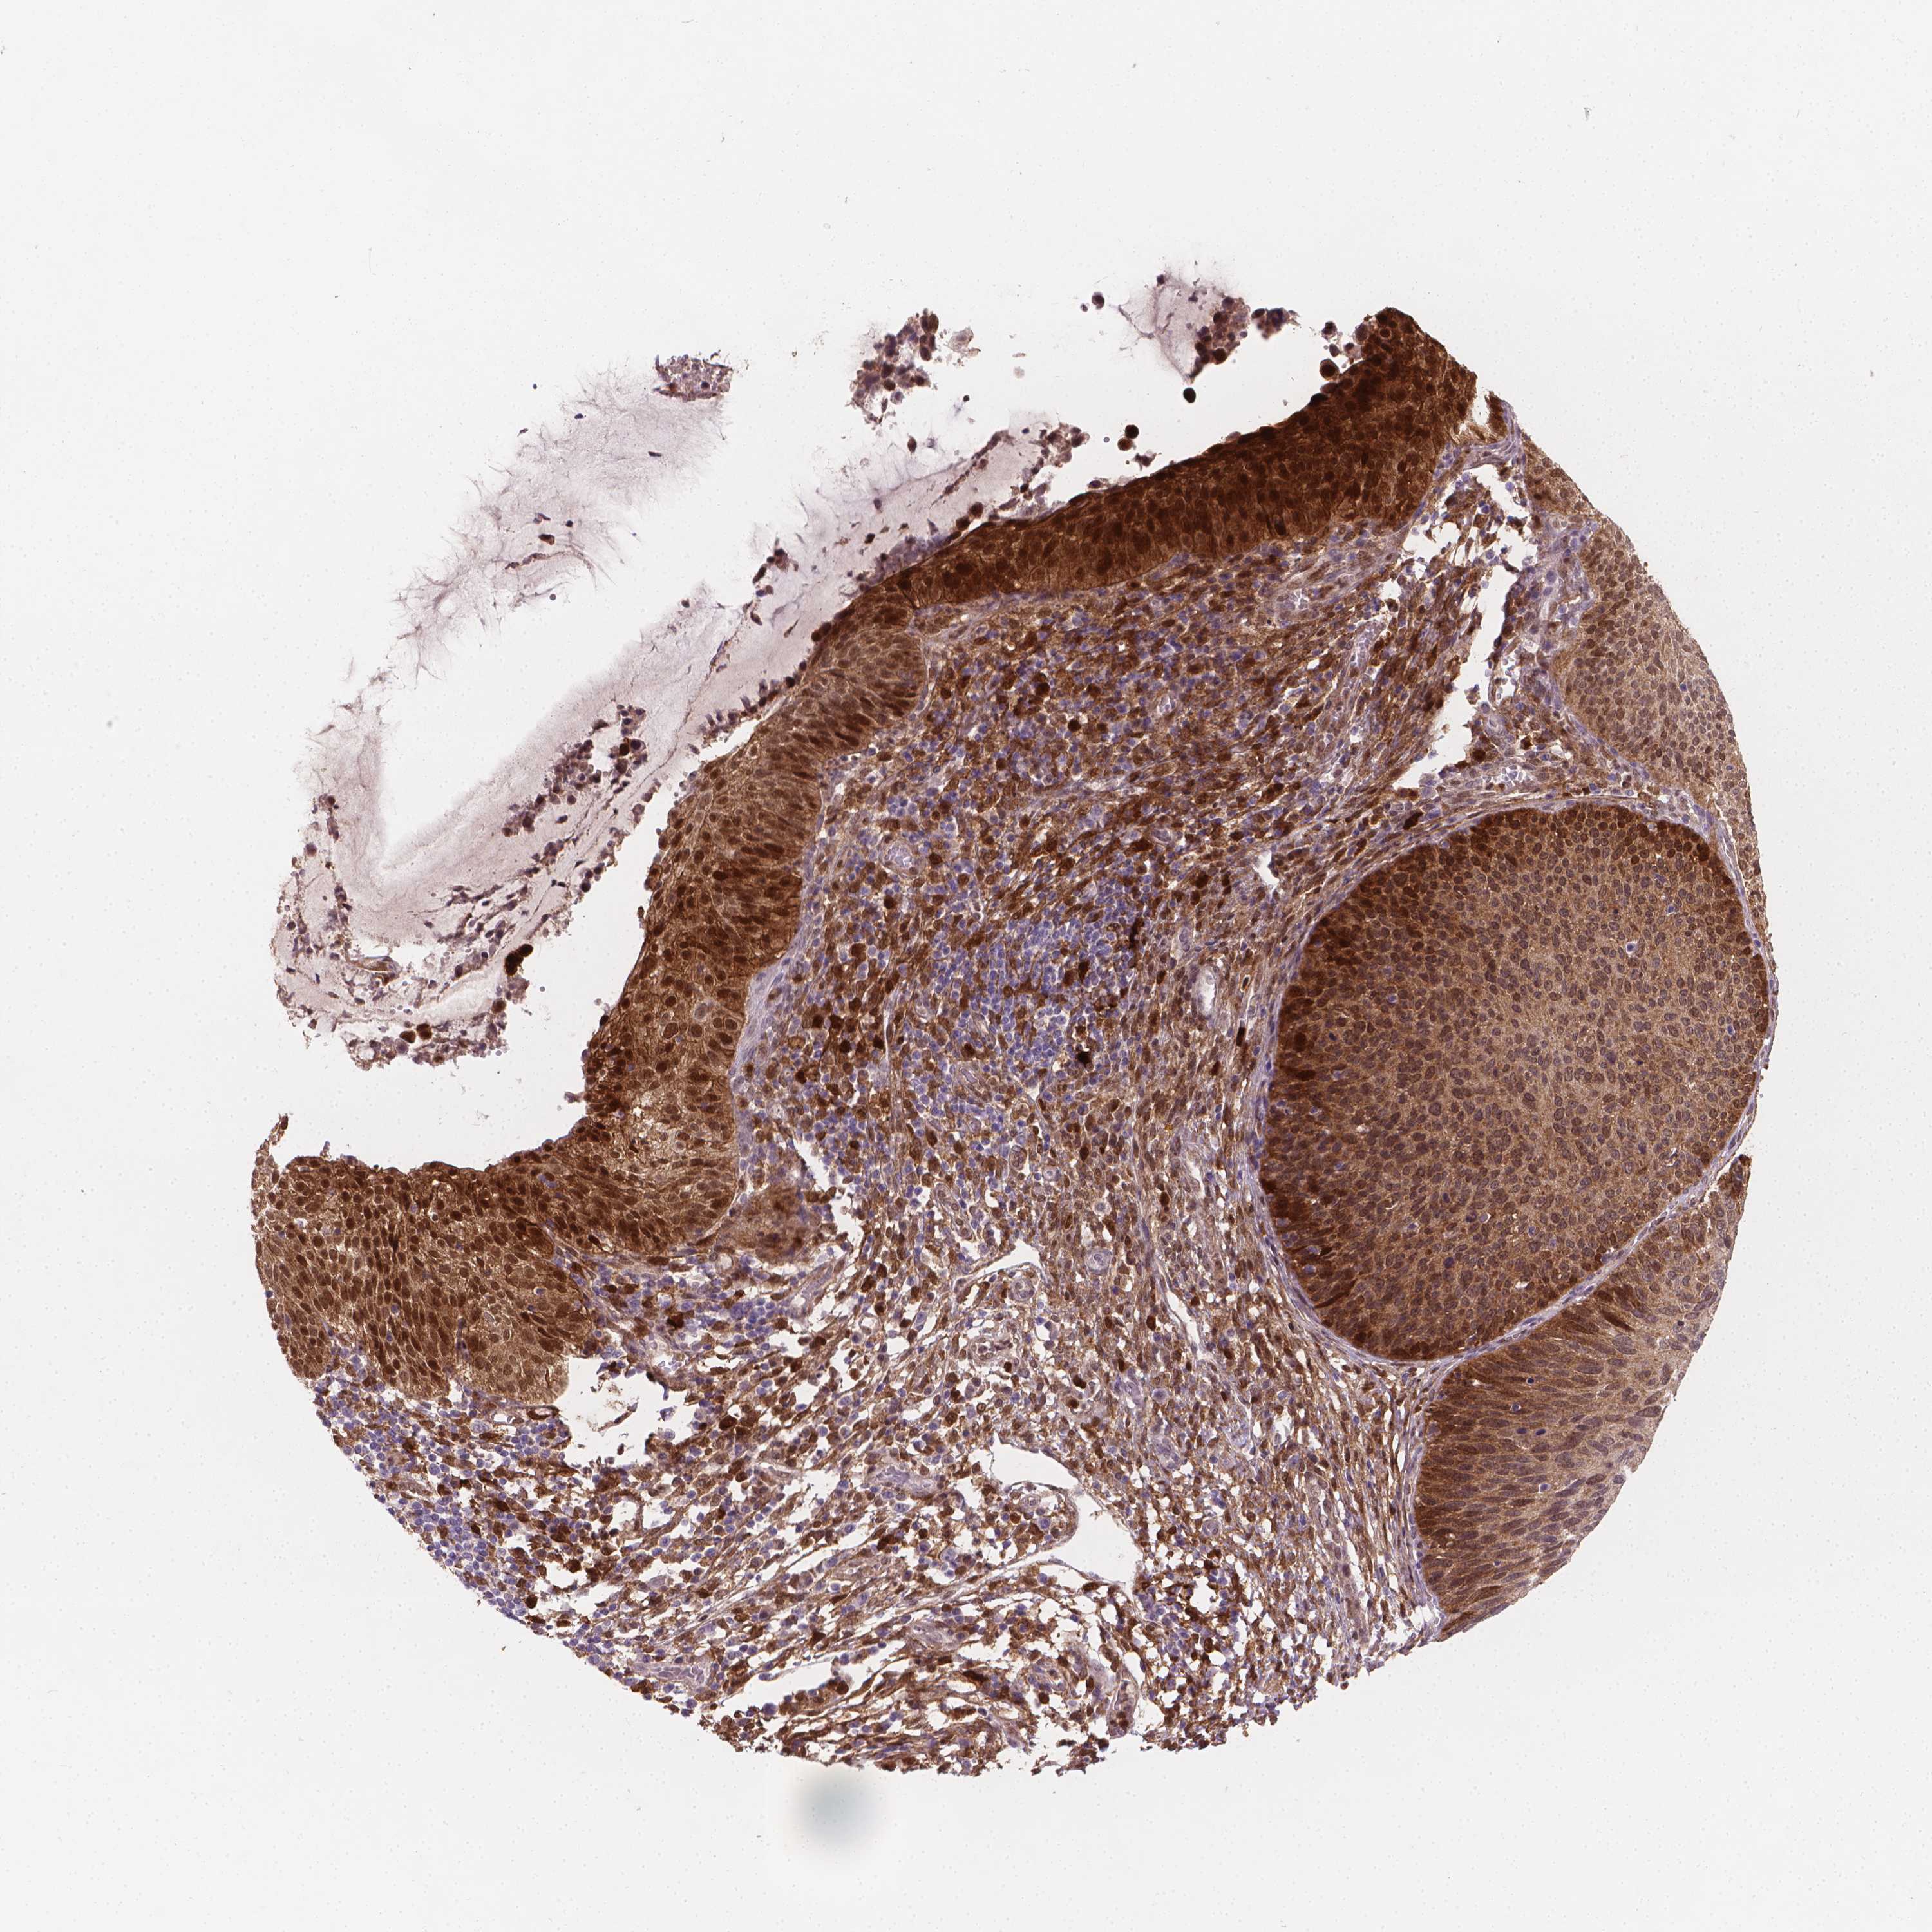

CERVICAL CANCER - Protein expressioni

A mouse-over function shows sample information and annotation data. Click on an image to view it in a full screen mode. Samples can be filtered based on level of antibody staining by selecting one or several of the following categories: high, medium, low and not detected. The assay and annotation is described here.

Note that samples used for immunohistochemistry by the Human Protein Atlas do not correspond to samples in the TCGA dataset.

Antibody stainingi

Antibody staining in the annotated cell types in the current human tissue is reported as not detected, low, medium, or high, based on conventional immunohistochemistry profiling in selected tissues. This score is based on the combination of the staining intensity and fraction of stained cells.

Each image is clickable and will lead to virtual microscopy that enables deeper exploration of all samples and also displays staining intensity scores, fraction scores and subcellular localization as well as patient and tissue information for each sample.

Antibody CAB004598

Staining

High

Medium

Low

Not detected

Intensity

Strong

Moderate

Weak

Negative

Quantity

>75%

75%-25%

<25%

None

Location

Nuclear

Cytoplasmic/membranous

Cytoplasmic/membranous,nuclear

Squamous cell carcinoma, NOS

Adenocarcinoma, NOS